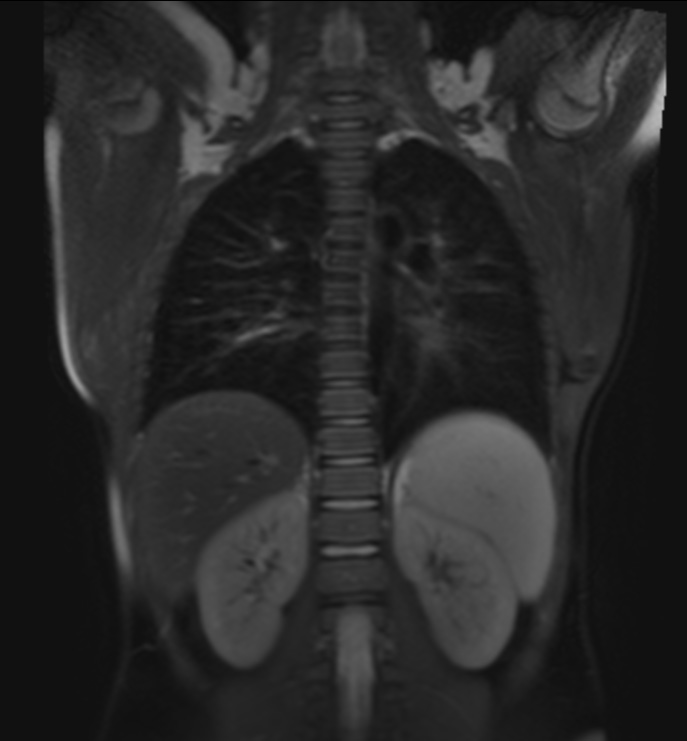

Рис 3. Т2-взвешенное изображение легких ребенка.

Цель: Разработка и внедрение в клиническую практику МРТ-исследований легких. Описание проекта: В настоящее время пациенты с сочетанной травмой обследуются методами многофазной компьютерной томографии с введением контрастного препарата. При этом пациент получает значительную дозу облучения: по медицинским показаниям, исследования могут регулярно повторяться. В то же время, МРТ позволяет без лучевой нагрузки получить изображения с различными типами контраста, что позволяет дифференцировать характер патологии. Традиционно считается, что МРТ не обладает достаточной чувствительностью при обследовании легких, однако современные методики МРТ позволяют получать диагностически информативные изображения – как при задержках дыхания(чтобы избежать артефактов движения), так и при свободном дыхании пациента. Задачей исследования является разработка и клиническая апробация МРТ протоколов сканирования легких. Результаты: Разработаны протоколы сканирования, ведется клиническая апробация.